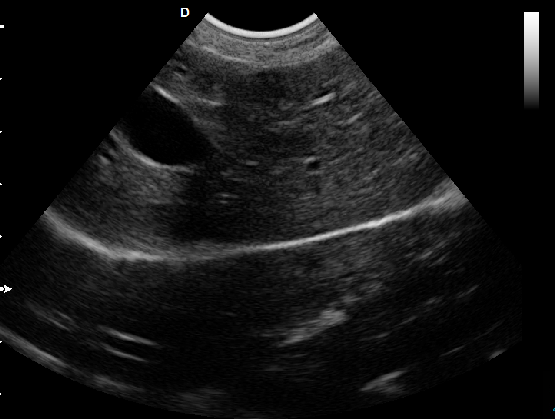

P5-VET手提式獸用彩超機心臟超聲檢查圖

心臟超聲檢查:

心臟超聲是唯一能動態(tài)顯示心腔內結構、心臟的搏動和血液流動的儀器,對人體沒有任何損傷。心臟的各個結構清晰地顯示在屏幕上。通過彩超的測量,醫(yī)生可了解瓣膜病變的程度以決定保守治療還是手術治療。心肌的增厚、心腔的擴大都要依賴彩超來判斷;對冠心病,彩超能直觀顯示心肌的運動狀況及心功能,向臨床醫(yī)生提示心肌缺血的部位。